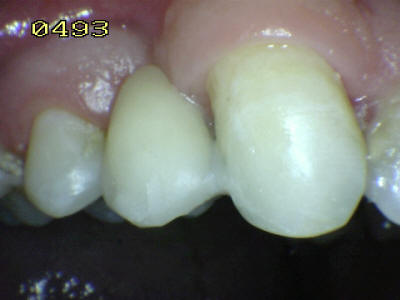

Vista vestibular. El matiz del póntico (flecha verde) se determino con el primer premolar (flecha marrón) Antes del tratamiento